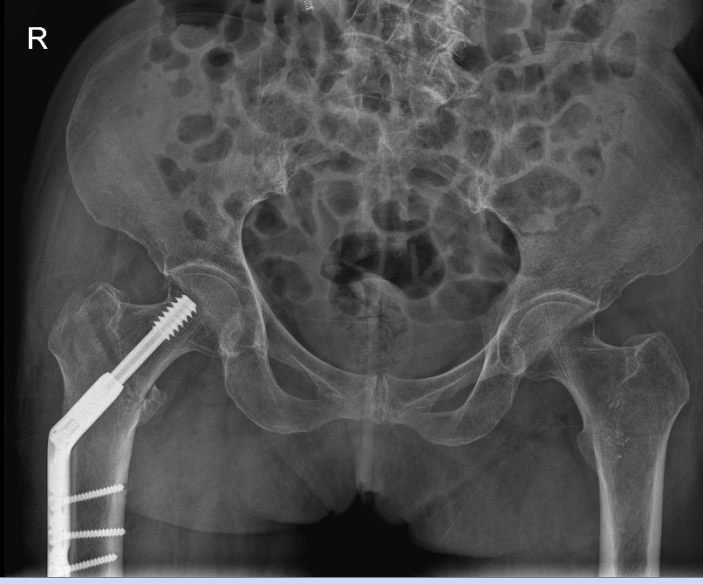

△骨科于15日、16日收治的另外兩位高齡患者

△術前

△術後